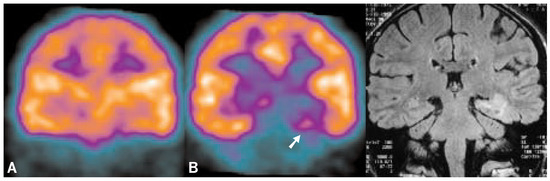

PET studies of memory

The publication of two discoveries [1, 2] set the ground for theories, experiments and clinical practice during the past 40 years in the neuroscience of memory. Since then, we know that memory is not supported by the total action of the entire brain but anatomically localizable like sensory and motor functions. It is the function of a neuronal network including both mediotemporal regions, particularly the hippocampal formations which were found to be indispensable for memory. Research with amnesic patients led to the next discovery that memory is not a unitary system but consists of at least five different subsystems which are subserved by different, though overlapping neuronal networks. In the following, the function of the “pioneer structure” hippocampus in the human was pinned down to episodic memory alone and became even further specified to learning/consolidation, novelty detection, deep processing, associative learning, and – not treated in this article – spatial learning.To further elucidate the function(s) of the hippocampal region in human memory we carried out two Positron Emission Tomography (PET) experiments testing the above hypotheses. The findings were straightforward: nothing challenged both hippocampal formations as much as establishing new semantic associations between previously unrelated words or pictures in memory. Full article

Figure 1